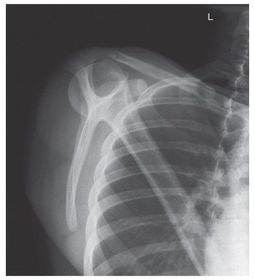

Which projections/positions are these? (top->bottom) TOP: Scapular Y-View _________________________ BOTTOM: AP External Rotation (greater tubercle in profile)

Which projection/position is this? Transthoracic Shoulder ___________________ ribs are blurred out from orthostatic breathing